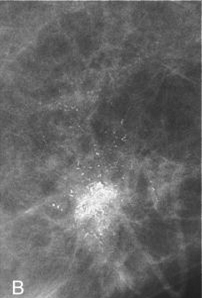

Αποτιτανώσεις υψηλής πιθανότητας για κακοήθεια (εικόνα Β)

Το πιο συχνό μαστογραφικό εύρημα που σχετίζεται με την ανάπτυξη πορογενούς καρκινώματος in situ (DCIS) είναι η παρουσία μικροαποτιτανώσεων σε ασυμπτωματικές γυναίκες. Χάρη στη διαρκή βελτίωση των διαθέσιμων απεικονιστικών τεχνικών και την ευρύτερη συμμετοχή των γυναικών στα προγράμματα προσυμπτωματικού πληθυσμιακού ελέγχου, σήμερα το DCIS αντιπροσωπεύει το 22%-45% όλων των διαγνωσθέντων καρκίνων του μαστού.

Φαίνεται ότι η μορφολογία των μικροαποτιτανώσεων έχει κάποια σχέση με την εξέλιξη, με τις υψηλής πιθανότητας για κακοήθεια αποτιτανώσεις να χαρακτηρίζουν τα high-grade DCIS, αυτά δηλαδή με υψηλό δυναμικό εξέλιξης σε διηθητική νόσο, και τις ενδιάμεσης πιθανότητας για κακοήθεια, άμορφες, να χαρακτηρίζουν μια εξελικτική διαδικασία από την άτυπη επιθηλιακή υπερπλασία ως τα low-grade DCIS, με χαμηλότερο δυναμικό εξέλιξης σε διηθητική νόσο.